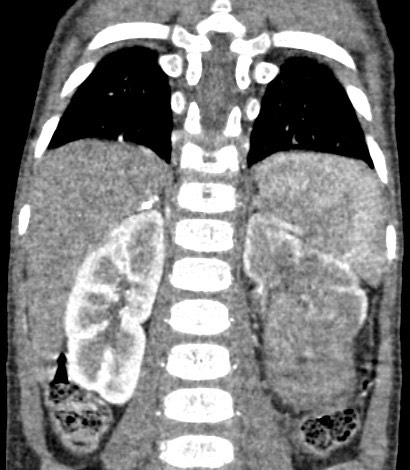

1387. Пациенту 4 лет с жалобами на кровь в моче, увеличение живота в размерах, снижением веса в течение месяца выполнена компьютерная томография, патологическим процессом, соответствующим клинико-рентгенологической картине считают опухоль